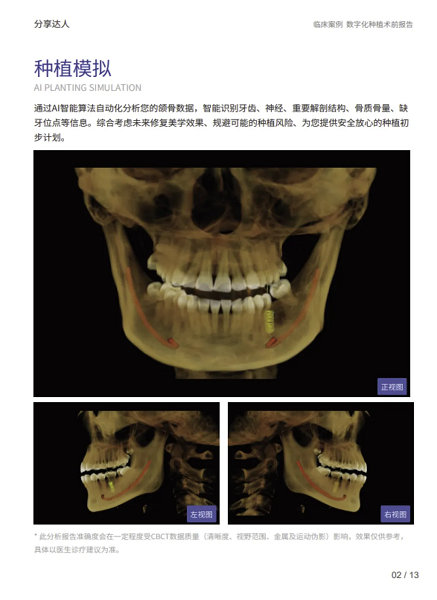

2.智能规划:从经验依赖到人机协同的进化

面对复杂手术规划,Dental X云平台能基于患者影像数据,由AI自动生成包含植入位置、角度和深度的三维规划方案。这不仅大幅缩短了规划时间,其科学性更为医生提供了可靠的参考基准,让医生能将核心精力集中于方案的个性化调整与优化,实现人机协同的决策模式。